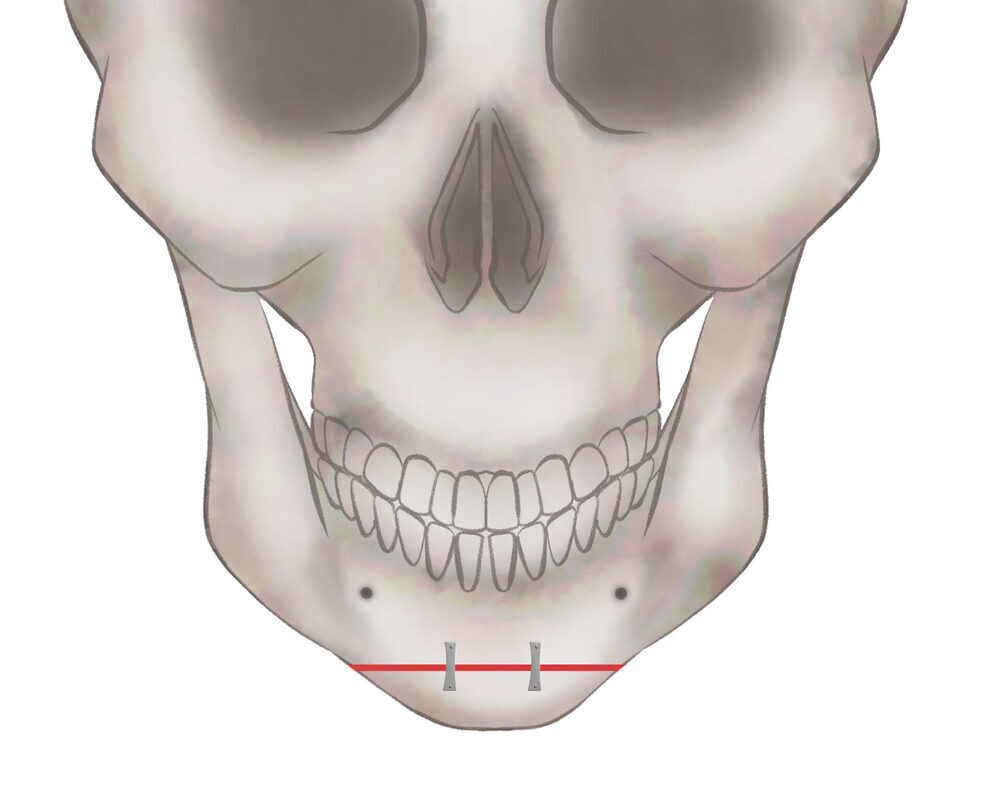

オトガイ骨削り・骨切り

パターン1

骨を切る、もしくは削ります

パターン2

骨を切る、もしくは削ります

パターン3−1

骨を切る、もしくは削ります

1.切開線をデザインします